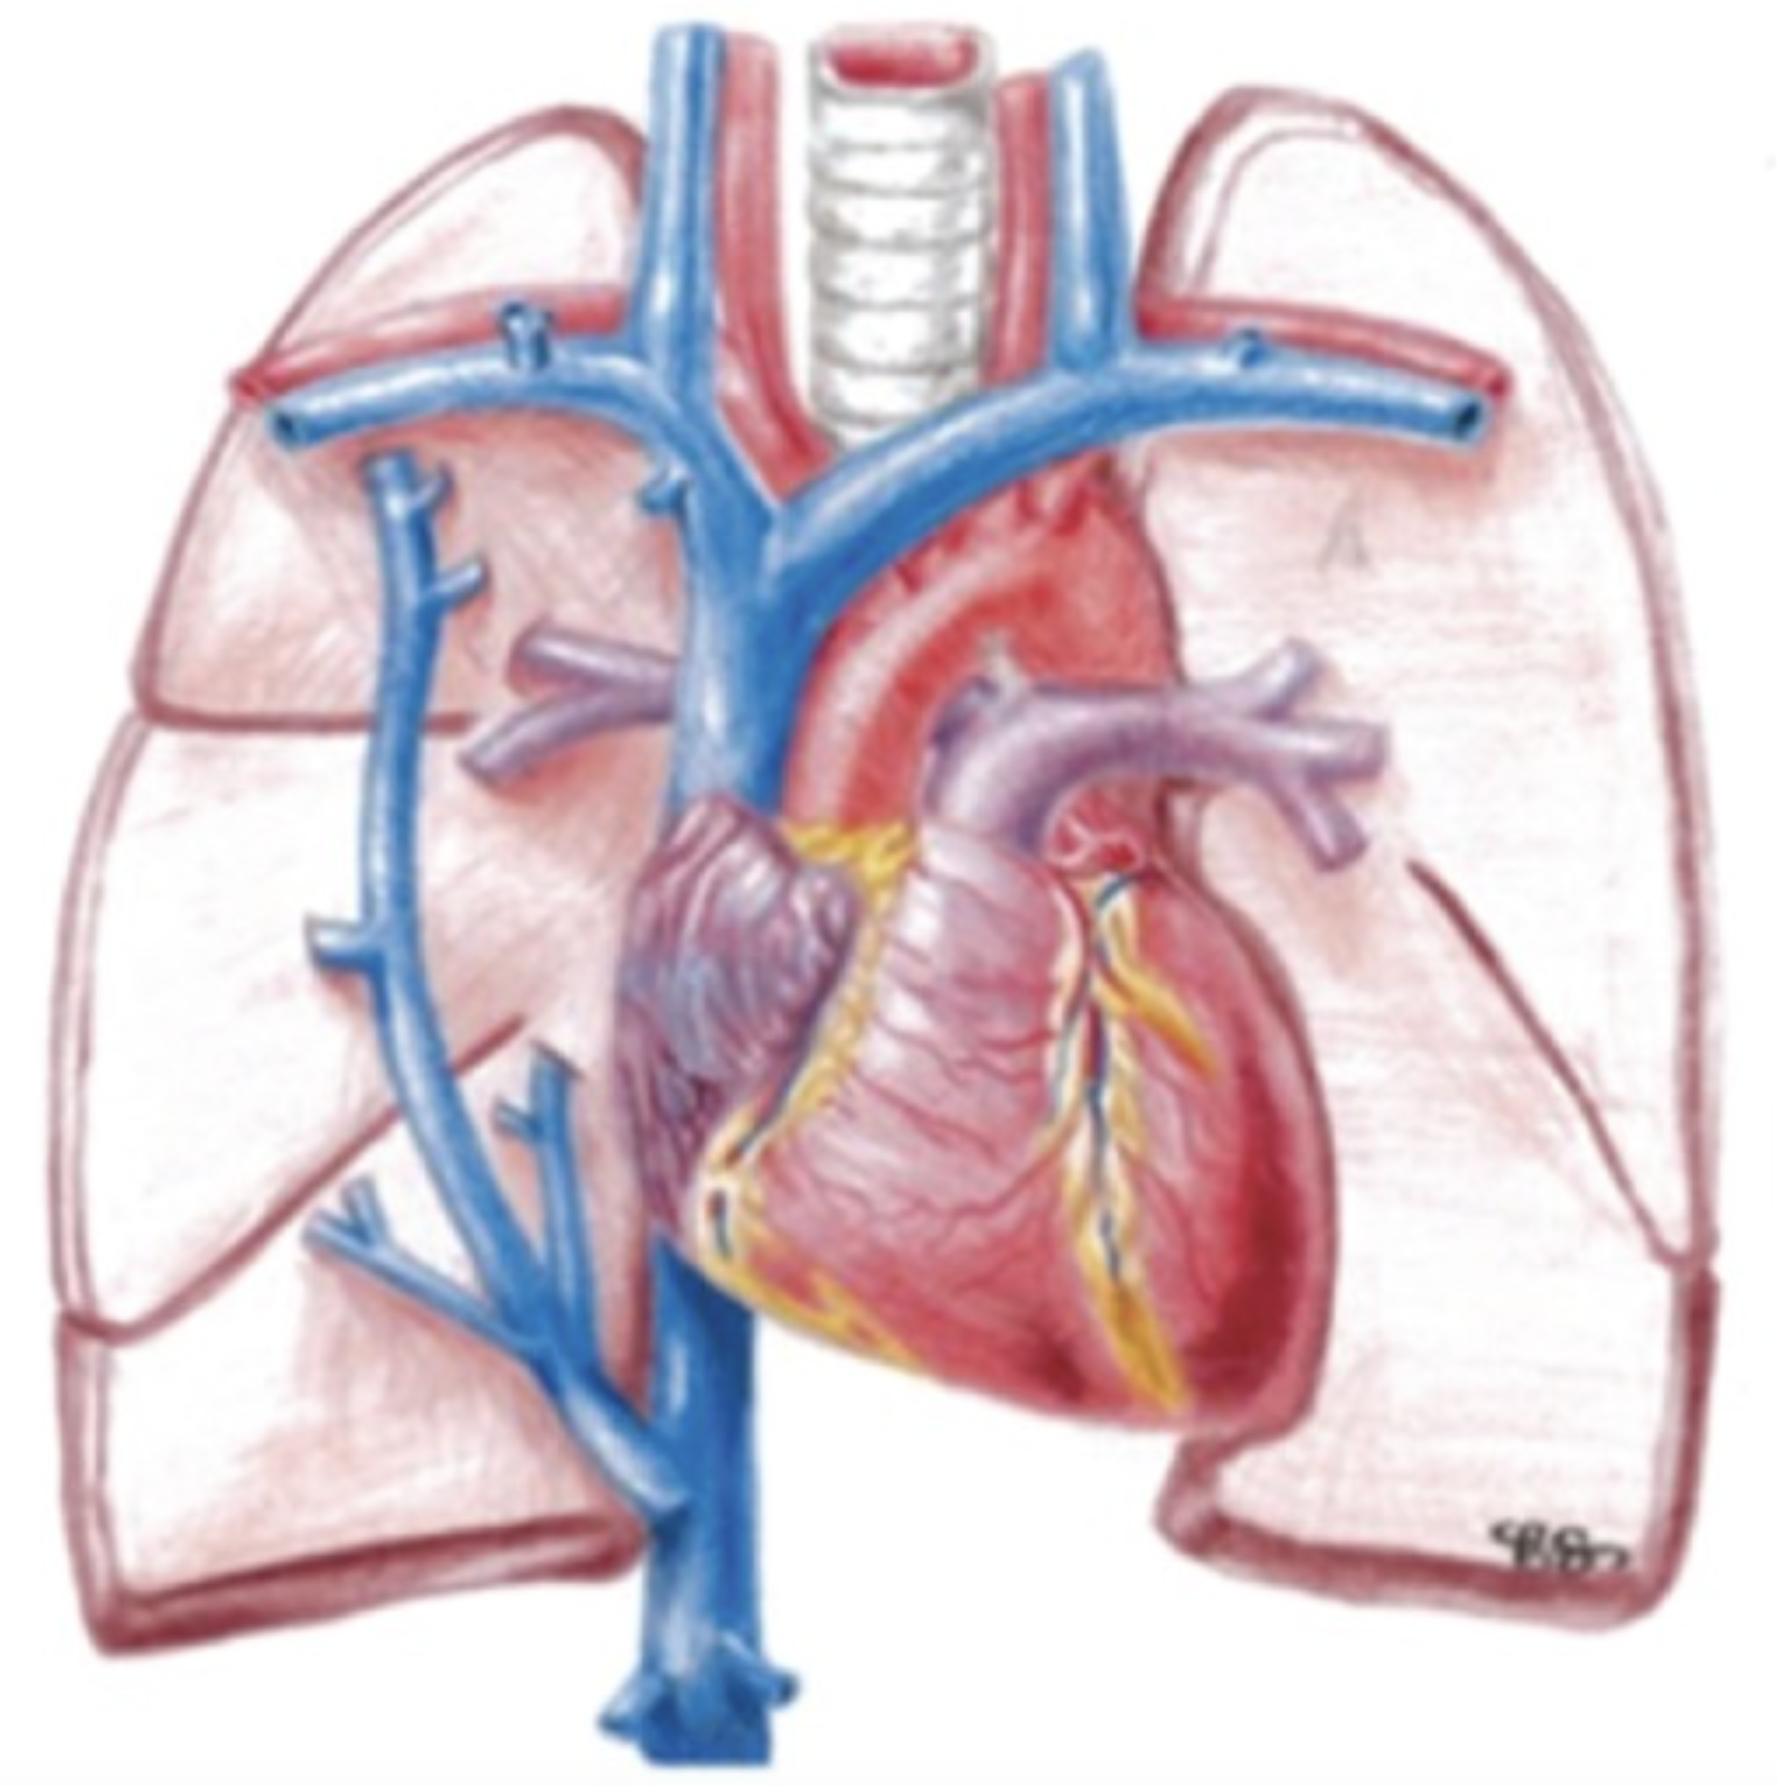

- 右房は通常,右第4肋間あたりに位置している

- 圧上昇の身体所見:右心系 ➜ 脈管内=頸静脈,脈管外=下腿浮腫/左心系 ➜ 脈管内=Ⅲ音,脈管外=湿性ラ音